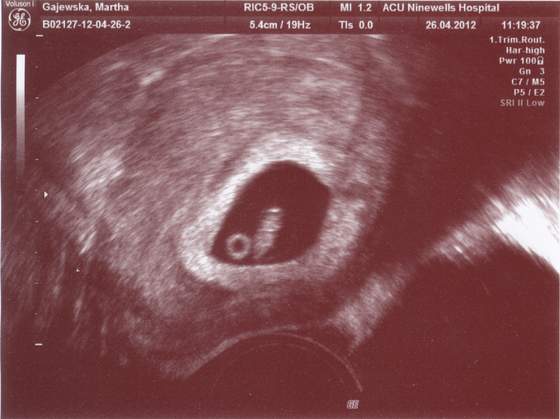

gienek - oto moje bysiory (niecale 6 cm)

Zobacz załącznik 471629